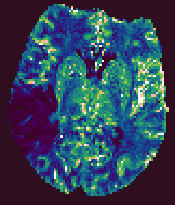

Brain Perfusion Output Parametric Images

The Brain Perfusion analysis produces five output images, that

have the same base name, but have the output parameter name

appended. These are:

- CBF. Cerebral blood flow, with units of mls blood / 100g tissue / minute.

- CBV. Cerebral blood volume, with units that indicate the blood

volume as a percentage of the total tissue volume.

- MTT. The mean transit time, in seconds.

- TTP. The time from contrast arrival to the peak in capillary concentration, in seconds.

- RMSE. A measure of the goodness of fit. This root-mean-square of the residuals between the

fitted curve and the time-series data.

These output images are in floating-point format, and can be

viewed using Jim. The output images will be of the same

image type as the first input image.

Example output images from the Brain Perfusion Tool.

|

| Cerebral Blood Flow |

Cerebral Blood Volume |

Mean Transit Time |

Time-to-Peak |